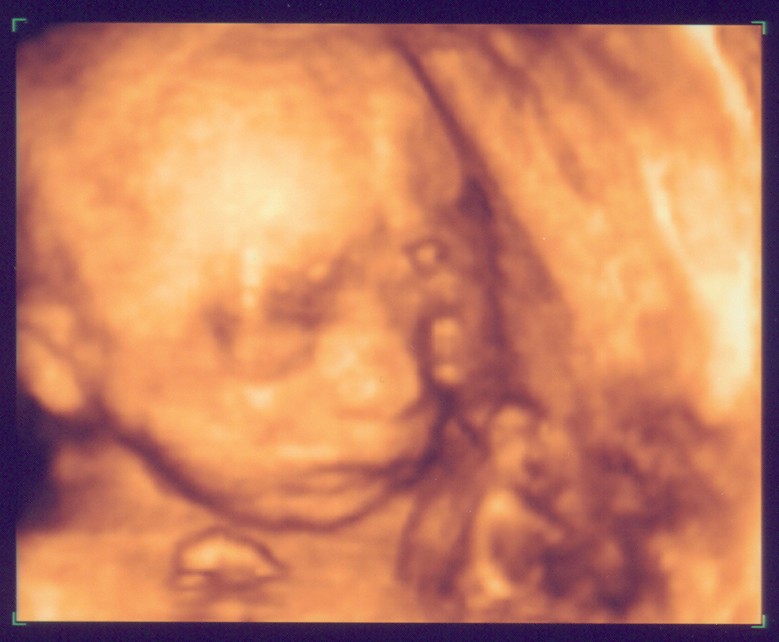

Unser "Maikätzchen" am 07.03.06

Eure Bilder sind echt toll. Wenn ich mich jetzt nicht allzu blöd anstelle, seht Ihr gleich das aktuellste von unserem Baby. Mit 3-D kann man schon sehr schön alles erkennen, aber wir haben auch ganz schaurige Bildchen. Kommt immer darauf an, wie die Mäuse posieren. :wink: